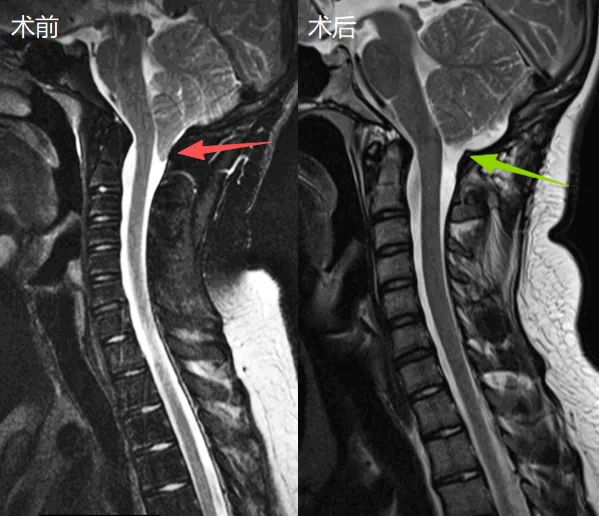

当一个运动员被一种先天性畸形缠上,他还能重回运动赛场吗?16岁的约翰曾患上一种名为Chiari畸形的神经外科疾病,这个病令他不得不暂时告别赛场,直到他等来一场手术,情况似乎开始变得...